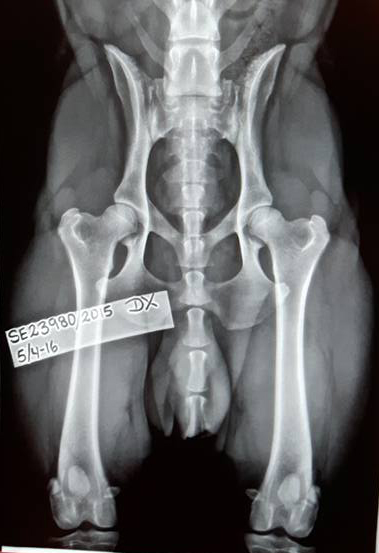

HD grad A, ED 0, patella ua/OK